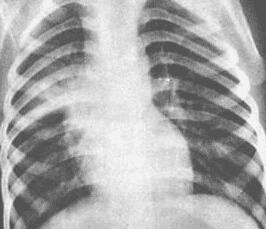

血行播散型肺结核是结核分枝杆菌一次或反复多次进入血液循环,造成肺部病变以及相应的病理、病理生理学改变和临床表现者称为血行播散型肺结核,造成全身多脏器病变时则称血行播散型结核病。血行播散型肺结核是一种危重结核病,由原发型肺结核发展而来,也可由其它结核干酪样灶破溃到血源引起。该病多见于儿童,成人亦可发生。随着人口老龄化和老年人寿命的延长以及结核病疫情的回升,老年血行播散型肺结核病有增多趋势。